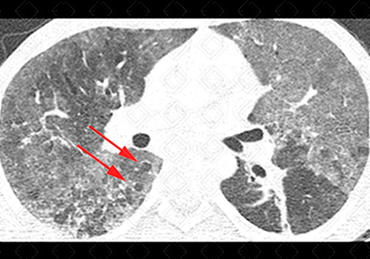

Texto alternativo para a imagem Créditos: Dra. Elazir Mota - Rio de Janeiro/RJ

Descrição da lesão: Tomografia computadorizada do tórax. Extensas opacidades em vidro fosco distribuídas difusamente pelo parênquima pulmonar associado a pequenos cistos à direita (setas vermelhas), num paciente sexo masculino, 15 anos, SIDA - transmissão vertical. A hipótese de pneumocistose deve ser sugerida e, no caso descrito, foi confirmada.

• Tomografia computadorizada do tórax: Opacidades em vidro fosco, difusamente distribuídas pelo parênquima, são os achados mais comumente observados. A ordem decrescente de acometimento: opacidades em vidro fosco, as consolidações alveolares, as alterações das vias aéreas (dilatações brônquicas e espessamento de paredes brônquicas), o espessamento de septos interlobulares, eventualmente formando o padrão de pavimentação em mosaico, as lesões císticas e os nódulos. Diante de uma história clínica adequada (paciente HIV+), o achado tomográfico de áreas em vidro fosco dispersas pelo parênquima associado a cistos pulmonares é muito sugestiva de pneumocistose.